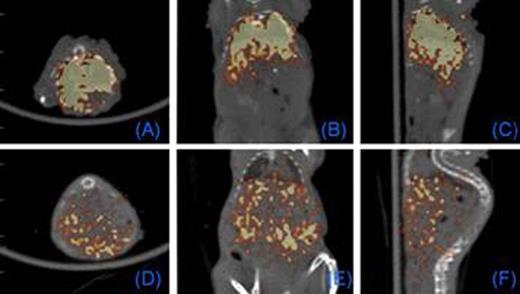

We first tested whether commercially available nanoparticles can be electro-transferred into cultured and primary human T cells. 43 nm diameter latex nanoparticles and 7 nm gold nanoparticles (GNPs) were electro-transferred into T cells and visualized by TEM and confocal imaging (Figure 1). We have modified GNPs on the surface with the chelator, diethylenetriaminepentaacetic acid (DTPA), for stable coordination with 111In followed by GNP PEGylation. We have shown that these radiolabeled GNPs can be readily electro-transferred into T cells suitable for combined single-photon emission computed tomography (SPECT) and computed tomography (CT) (Figure 2). We used a clinical SPECT/CT scanner to detect 111In-GNP in T cells (∼2.1 × 104 nanoparticles/cell) at a sensitivity of ∼760 cells/mL. After developing electroporation protocols of nanoparticles and in vivo imaging of 111In-GNPs, additional sensitivity was achieved by modifying the chelating chemistry using the macrocyclic chelator, 1,4,7,10-tetraazacyclododecane-1,4,7,10-tetraacetic acid (DOTA), to bind 64Cu to GNPs, increasing the number of gold particles/cell, and using 64Cu-labeled GNPs for imaging by positron emission tomography (PET). Before tail vein injection to a mouse, 11.4 mCi was detected from 10 million T cells (suspended in 300 μL PBS) electroporated using a BTX ECM830 device with the following settings: 1 kV/cm, 4 ms duration, single square pulse (Figure 3). The estimated concentration of nanoparticles transferred into T cells was ∼2.3 × 105 nanoparticles/cell as determined by a gamma counter (2470 Wizard, PerkinElmer) and nanoparticle titration. While 20 nm GNPs were used for 111In labeling, 7 nm GNPs were chosen for 64Cu labeling because of the improved (10-fold) electroporation efficiency.

Figure 3.

PET Imaging of T cells loaded with intracellular 64Cu-GNPs. 0.5 (A-C) and 18 (D-F) hours after tail vein injection of T cells. Each panel: axial, coronal, sagittal views, respectively.